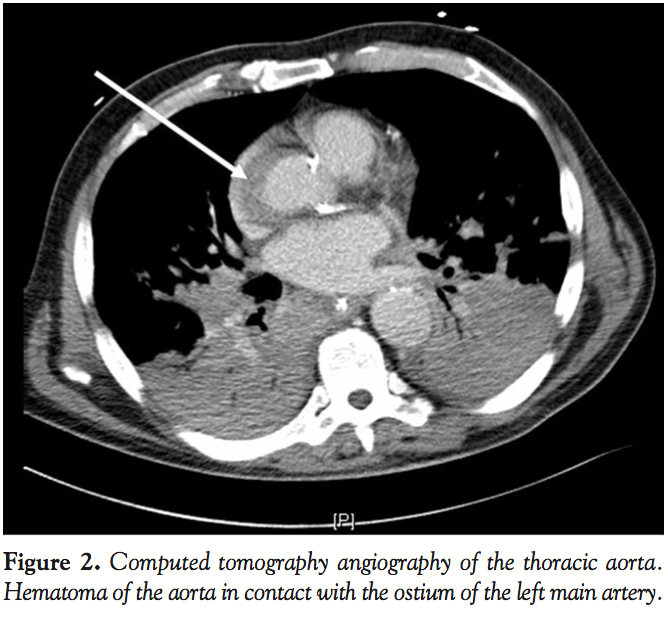

A computed tomography angiogram of the aorta was performed. This exam showed a non-circulating hematoma of segment I of the aorta extending from the anterior wall to the right wall. The thickness of the hematoma was 14 mm and aortic diameter was 55 mm. The hematoma ran from segment 0 of the aorta to segment I. It crushed the ostium of the left main artery (Figure 2). Segments II and III of the aorta and the supra-aortic arteries were not involved in the dissection.